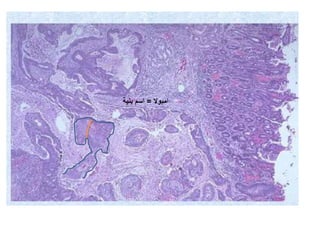

The document summarizes key aspects of liver and gallbladder anatomy and histology. It notes that hepatocytes in the liver have abundant mitochondria and are surrounded by peri-sinusoidal spaces filled with microvilli. The gallbladder stores and concentrates bile produced by the liver through absorption and secretion. The gallbladder can become inflamed or damaged due to blockage and accumulation over time.